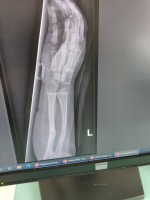

Madzia choruje na wrodzoną łamliwość kości typu III (osteogenesis imperfecta) – rzadką, genetyczną chorobę tkanki łącznej, która powoduje skrajną kruchość kości. Złamań doznała już w życiu płodowym, a jej organizm nie produkuje kolagenu. Choroba jest nieuleczalna, a leczenie ma charakter objawowy i obejmuje stałą rehabilitację, liczne operacje, stabilizację kości oraz specjalistyczną farmakoterapię. Dziewczynka ma za sobą już kilka poważnych zabiegów oraz kilkanaście podań leków wzmacniających kości. Przed nią kolejne operacje i intensywna fizjoterapia, bez której trudno byłoby myśleć o większej samodzielności.

Foto: Licytacje dla Madzi Sulki.